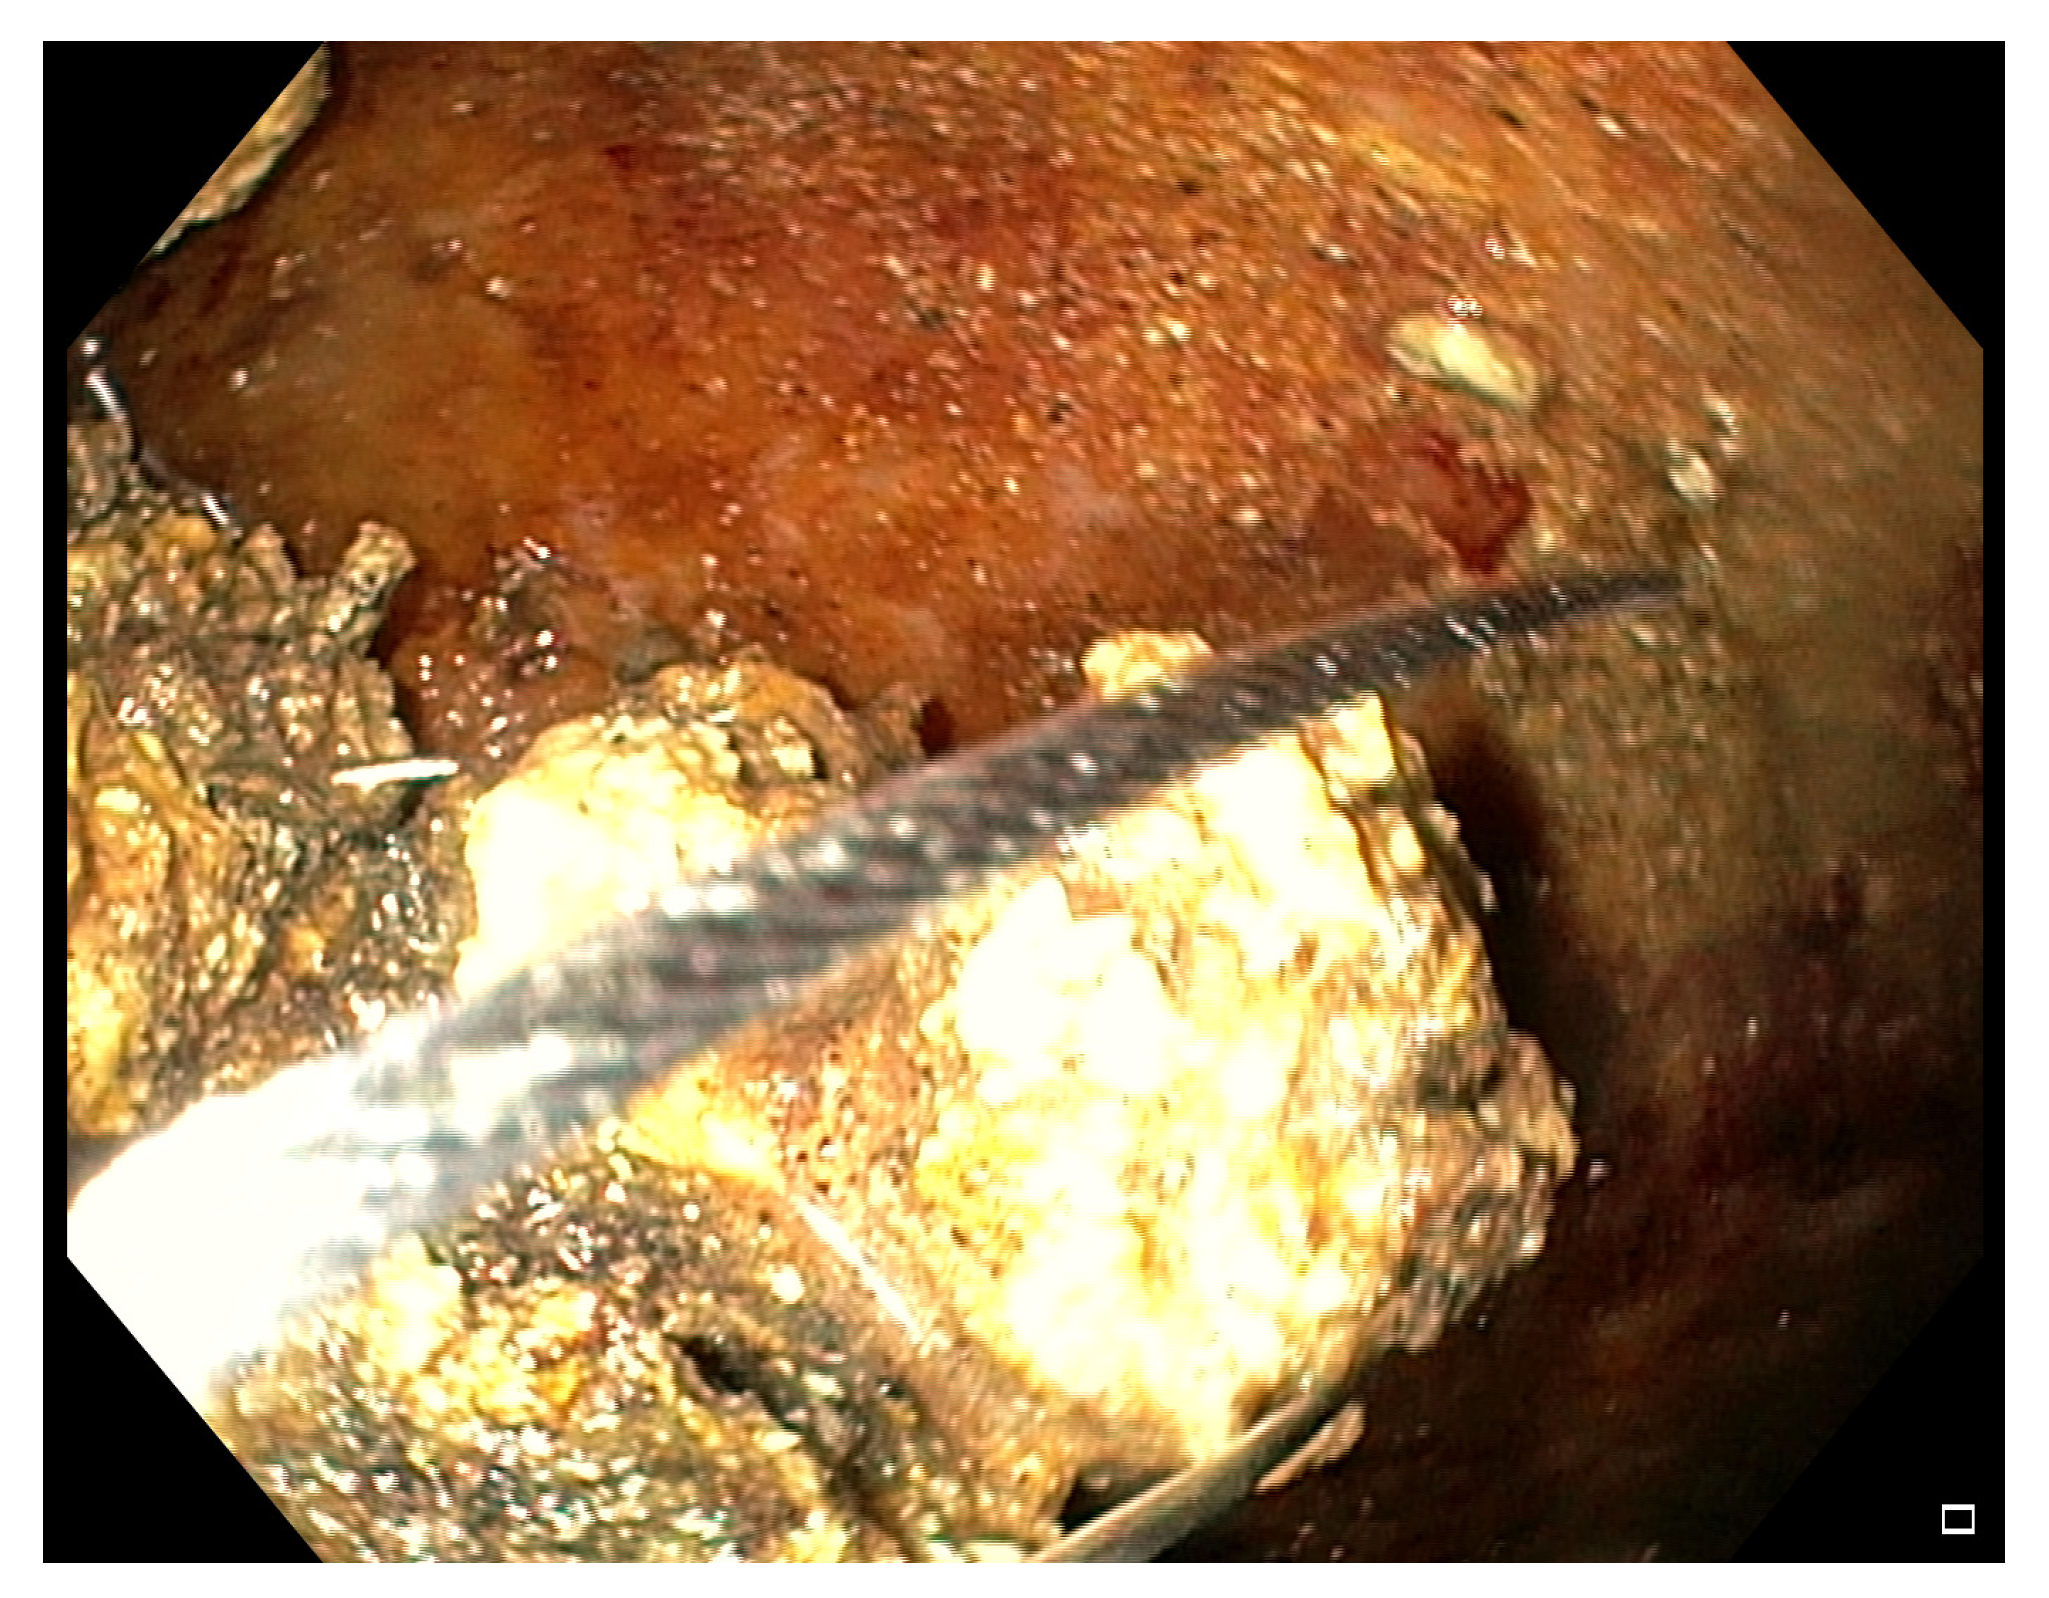

- EC-LAMS: the deployment catheter is positioned on the selected point on the gastric/duodenal wall. The activation of the electro-cautery tip allows direct passage of the catheter into the collection under EUS guidance. The distal flange of the LAMS is deployed, and the next steps are the same as the LAMS (Figure 3) [50].